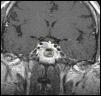

Mujer de 35 años con antecedentes personales de hipertensión arterial y diabetes mellitus tipo 2 de reciente comienzo que consultó por oligomenorrea de 6 meses de evolución acompañada de galactorrea bilateral. En la exploración destacaba, además, una obesidad central con signos de hipercortisolismo: estrías violáceas abdominales, cara de luna llena y giba de búfalo. Por todo esto se solicitaron hormonas hipofisarias y cortisol libre urinario. Los resultados fueron los siguientes: prolactina de 425ng/dl (VN<25ng/dl), cortisol libre urinario de 450μg/24h (VN<100μg/dl), cortisol basal de 35μg/dl (VN<25μg/dl), corticotropina basal de 72pg/ml (VN<50pg/ml), GH de 1,2ng/dl (VN<5ng/dl), IGF-I de 245ng/ml, TSH de 2,3mUI/ml (VN de 0,5-5μUI/ml) y tiroxina libre de 15pg/ml (VN de 8–18pg/ml). Ante los hallazgos analíticos se solicitó una resonancia magnética hipofisaria, que demostró un macroadenoma invasor del seno cavernoso derecho (fig. 1). El estudio inmunohistoquímico final fue el reseñado (tabla 1).